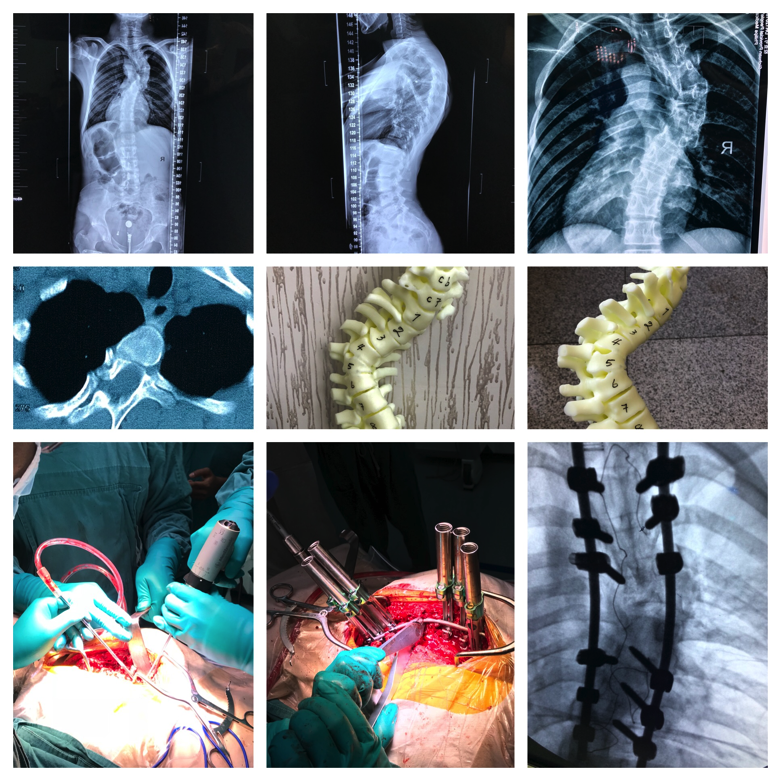

神经肌肉型侧弯